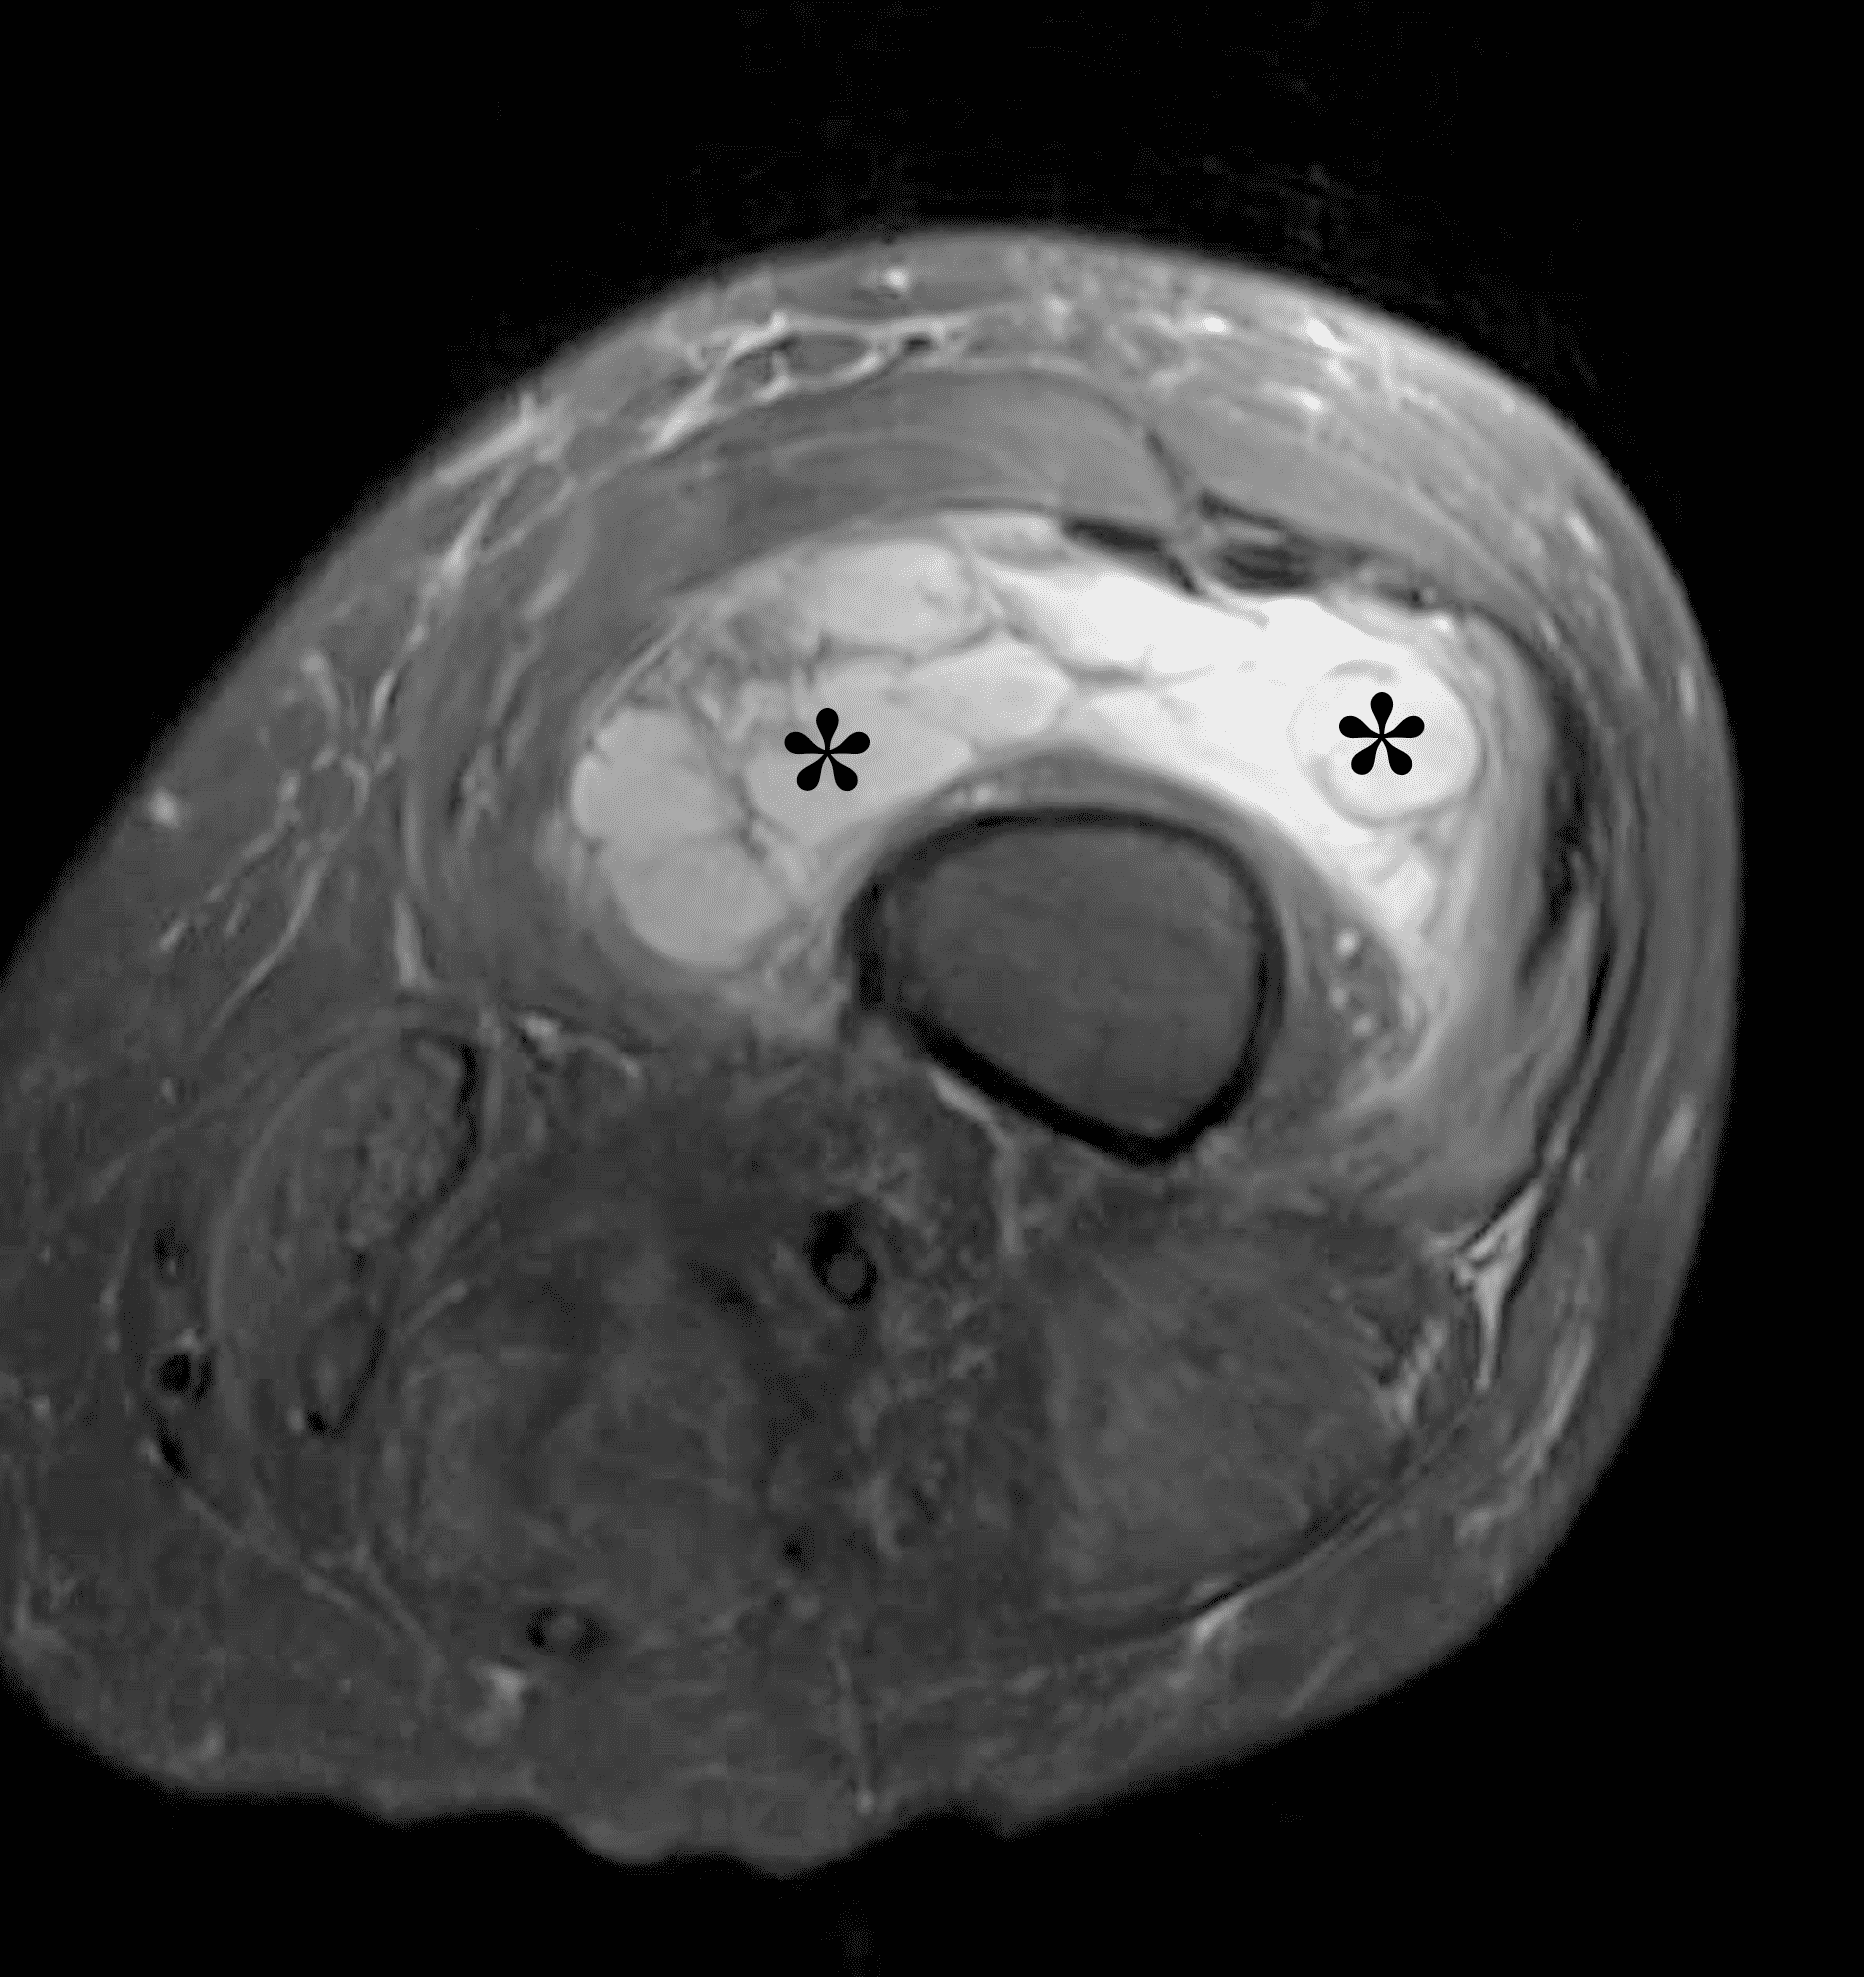

Figure 5: Primary synovial chondromatosis in the knee joint. (5A) Sagittal fat-suppressed, fluid-sensitive image demonstrates diffuse, heterogeneous intermediate and hyperintense signal synovially-based masses throughout the joint (asterisks). (5B) Lateral radiograph shows corresponding faint “ring and arc” calcifications (arrows).